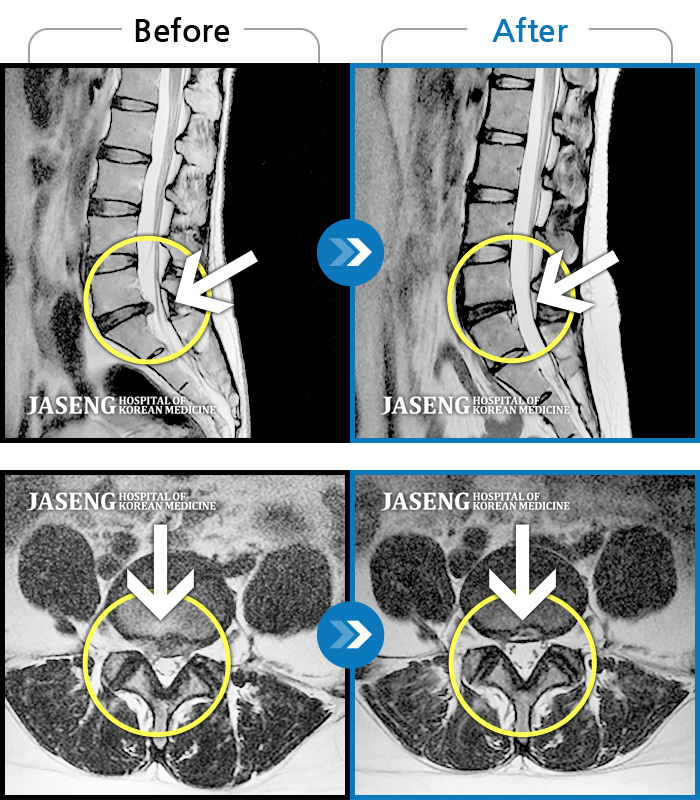

허리디스크

분당 · 진은석 원장

허리가 끊어질 것 같은 통증에 앉거나 눕기도 어려운 상태였습니다. 또한 양쪽 다리 모두 다리로 내려가는 방산통이 심했습니다.

촬영시기

2021.05.17 ~ 2021.11.17

2021.12.03

조회수 532